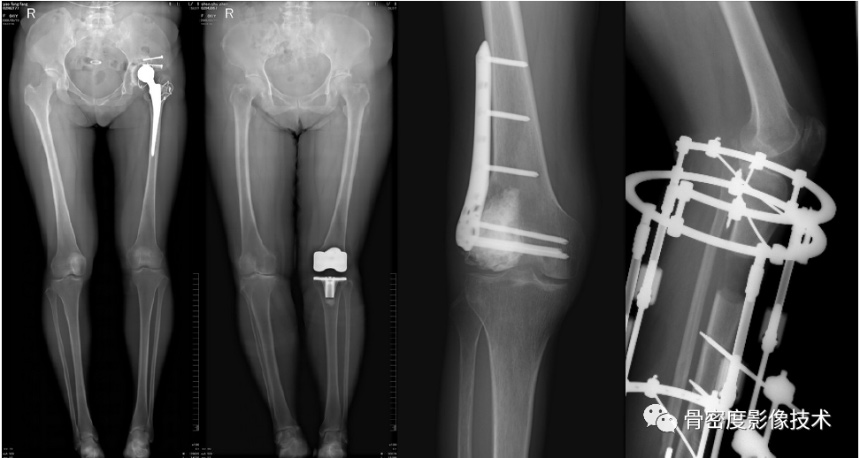

应用适应症:全下肢摄影—人工髋关节、膝关节置换以及下肢不等长畸形的矫正和O、X型腿畸形的矫正。可进行骨密度检查和负重全下肢扫描。

图5 股骨颈骨质量术前评估联合股骨、膝关节置换等术后评价